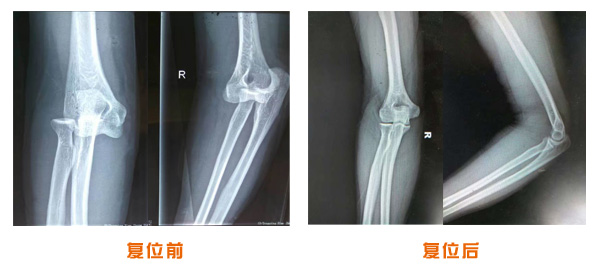

肥城市安駕莊梁氏骨科醫院是一所以梁氏手法正骨配合膏藥為特色的現代化專科醫院。

梁氏骨科術始創于清雍正年間,歷經八代,至今已有三百年歷史。據1929年泰安縣志載“梁瑞圖先生,字增生,號蓮峰,安駕莊人,精岐黃并發明接骨,凡跌打車凡跌打車軋皮不破而碎骨者......【詳細】 |